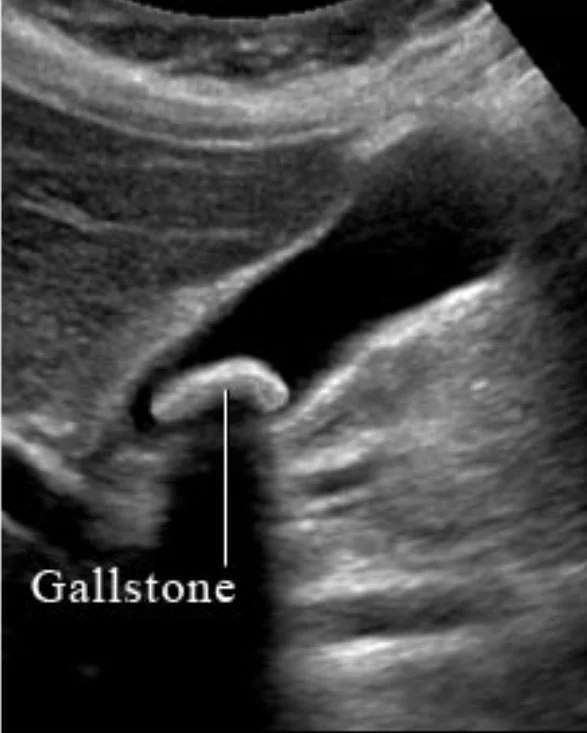

Private Abdominal Ultrasound in Portsmouth and Warsash In Hampshire: What It Can and Can’t Detect

If you’re dealing with abdominal pain, bloating, nausea or abnormal blood tests, an abdominal ultrasound can be a quick, safe first step. Here’s what it shows, how to prepare (including fasting), and what to expect — with a same-day digital report.